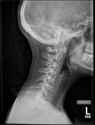

Is your neurologist picrel lmao. Get a new neurologist

I went to the ER recently during a very bad dizzy flare (couldn't walk without a rolling bag) and asked for a neck X-ray which they reluctantly gave me, and it confirmed my straight neck.